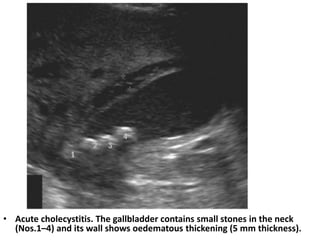

• Acute cholecystitis. The gallbladder contains small stones in the neck

(Nos.1–4) and its wall shows oedematous thickening (5 mm thickness).

• Acute cholecystitis.The gallbladder contains small stones in the neck (Nos.1–4) and its wall shows oedematous thickening (5 mm thickness).